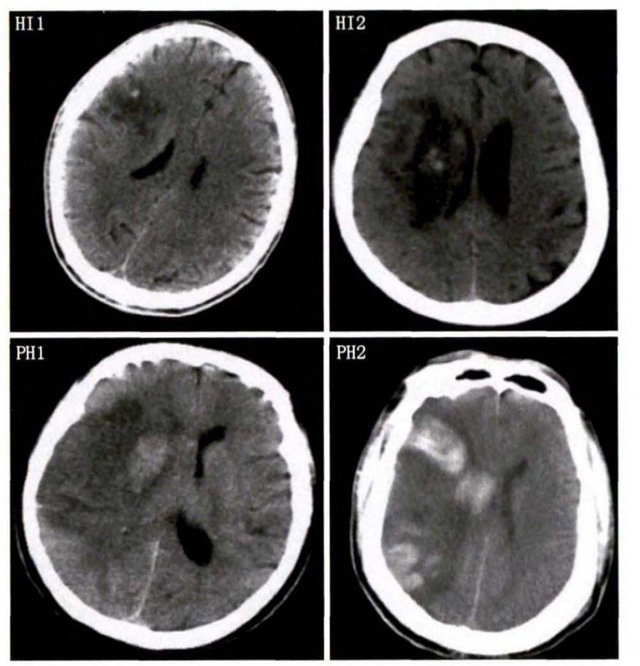

中、老年病患,有動脈粥樣硬化及高血壓病等腦卒中的危險因素,發(fā)病結合神經(jīng)系統(tǒng)癥狀和體征,應當考慮急性腦梗死的可能。再經(jīng)腦CT/MRI發(fā)現(xiàn)梗死灶,或排除腦出血、炎癥性疾病等,診斷即可確定。腦梗死有時頗似小量腦出血的臨床表現(xiàn)。腦栓塞在任何年齡都可以有發(fā)病的風險,可以在幾秒到幾分鐘達到頂峰。會有偏癱不能說話等局部神經(jīng)功能損壞。栓子來源很種,可能是冠心病、心肌梗塞、心內(nèi)膜炎等。合并心房纖顫,結合其他臟器官的支持診斷,CT跟磁共振都可以檢查確定栓塞位置數(shù)量還有是不是有伴發(fā)出血等問題??梢詭椭\斷。

中老年有高血壓糖尿病發(fā)病病史,起病神經(jīng)功能缺損癥狀,臨床表現(xiàn)為腔隙綜合征,即可初步診斷本病。如果CT或磁共振證實有與神經(jīng)功能缺失一致的腦部腔隙病灶, 符合大腦半球或腦干深部的小穿通動脈病變,即可明確診斷。少數(shù)患者隱匿起病,無明顯臨床癥狀,在影像學檢查時發(fā)現(xiàn)。